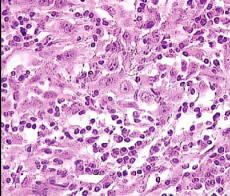

Fig. 1 – Lymphoepithelial-like carcinoma of the parotid gland. (A and B) Infiltrative but circumscribed cellular proliferation separated from the adjacent parotid gland parenchyma (left); the proliferation includes clusters of lighter-staining neoplastic ... Get Document